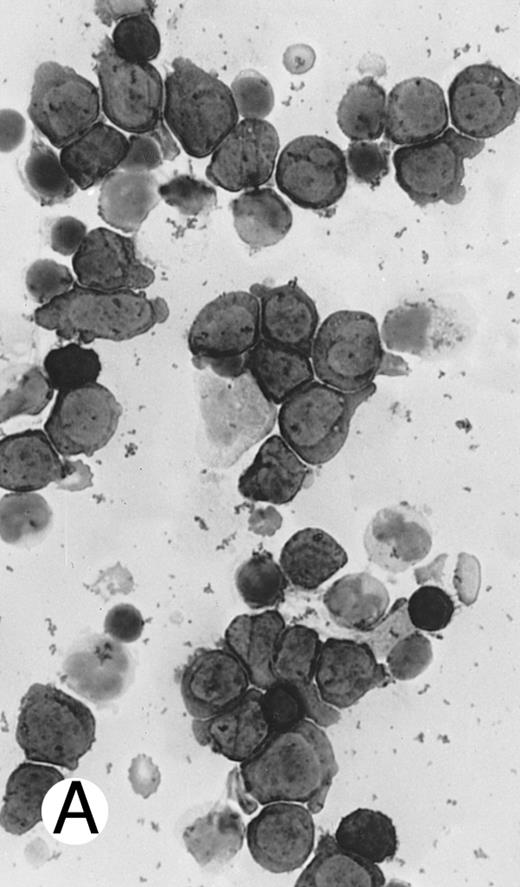

Two different cases of aggressive NK cell leukemia/lymphoma. (A) Peripheral blood shows increased large granular lymphocytes, most of which are mature-looking (case no. 36). The cell in the center is slightly less mature. (B) Buffy coat smear shows immature large granular lymphocytes with more open chromatin and distinct nucleoli (arrows) (case no. 37). Myeloid cells are seen in the background.

There were very few to numerous granular lymphocytes in the peripheral blood. Some of the granular lymphocytes were indistinguishable from normal large granular lymphocytes, with round nuclei, dense chromatin, and pale cytoplasm with fine azurophilic granules (Fig 5A). Some granular lymphocytes had larger nuclei with more open chromatin and distinct nucleoli (Fig 5B); occasional nuclei could show indentations. The azurophilic granules were sometimes large and coarse. There were also circulating normoblasts and immature myeloid cells. Marrow involvement ranged from subtle to extensive. In histologic sections, irrespective of site, there was a monotonous infiltrate of medium-sized cells with round nuclei and fairly condensed chromatin (Fig 6). Karyorrhexis was prominent. The infiltrate was diffuse, interstitial, or angiocentric.